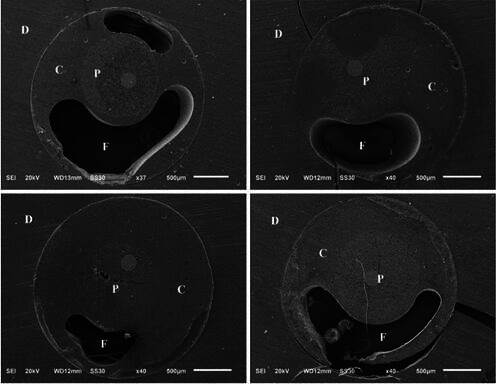

This study evaluated the bond strength (BS) of conventional, anatomized, adjustable, and CAD/CAM fiberglass post systems. Forty maxillary canine roots were weakened, endodontically treated, and divided into four groups (n=10). A slice from each of the three sections (cervical, middle, apical) of the root canal was subjected to the push-out test and the failure pattern was subsequently analyzed. The most apical slice was subjected to analysis of the cementation line thickness by scanning electron microscopy (SEM). Data regarding the BS and cementation line thickness were subjected to the Shapiro-Wilk normality test followed by the variance and Tukey tests. Data failure patterns were expressed as a percentage and submitted to the chi-square test. Conventional fiberglass posts had the lowest BD compared to the other fiberglass posts (p<0.05). All fiberglass posts exhibited a higher percentage of adhesive failures to dentin. The SEM demonstrated a thicker cementation line for the conventional post compared to the other groups (p<0.05), as well as gaps and voids in the cementing material. The anatomized, adjustable, and CAD/CAM milled fiberglass post systems demonstrated a superior BS and adaptation to the root dentin compared to the conventional fiberglass post.